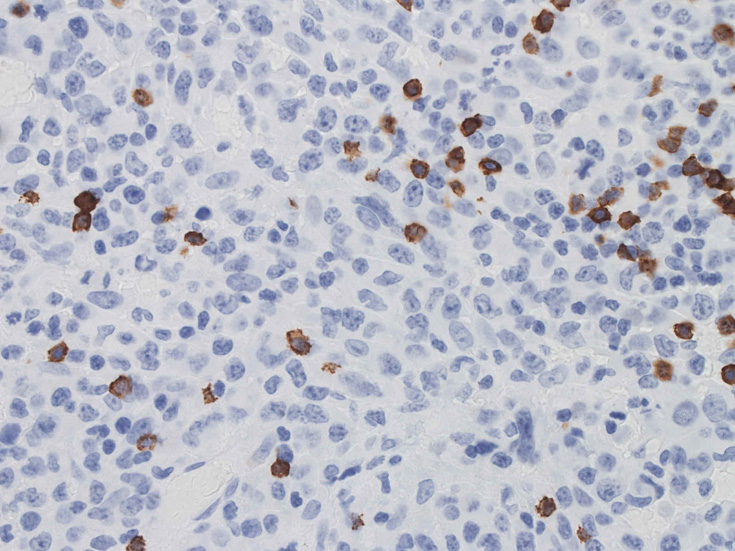

免疫染色の所見

CD30はほぼ全ての腫瘍細胞に陽性となる。膜とゴルジ装置が染まり, 図のように細胞質内に斑点状の染まりが認められます。増殖細胞はCD3, CD20陰性.

この症例では多くの腫瘍細胞がCD5陽性となり、CD30と同じ染色パターンを呈した。